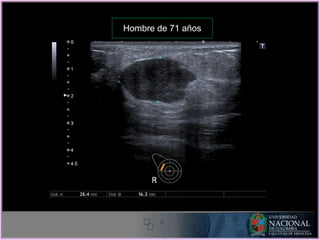

Indicaciones:

1. Exámen diagnóstico:

• Jóvenes menores 40 años.

• Lactancia y embarazo.

• Procesos inflamatorios o infecciosos

• Mama masculina.

• Evaluación de prótesis.

• Seguimiento de lesiones benignas.

ECOGRAFIA - Indicaciones

Hombre de 71 años

Indicaciones: 1. Exámen diagnóstico: •Jóvenes menores 40 años. • Lactancia y embarazo. • Procesos inflamatorios o infecciosos • Mama masculina. • Evaluación de prótesis. • Seguimiento de lesiones benignas. ECOGRAFIA - Indicaciones